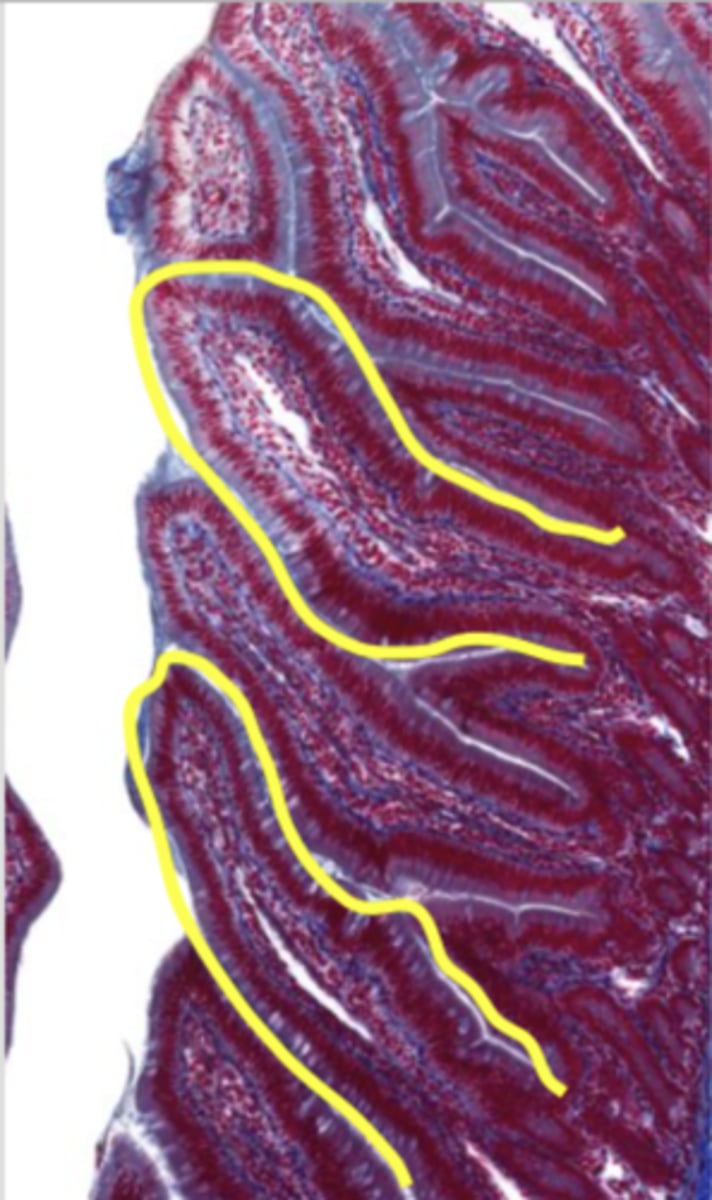

cardiac stomach (histology)

simple columnar epithelium

what kind of epithelium lines the mucosa of the cardiac stomach?

gastric pit (cardiac stomach)

lumen (cardiac stomach)

mucosa (cardiac stomach)

mucosal epithelium (cardiac stomach)

lamina propria (cardiac stomach)

muscularis mucosa (cardiac stomach)

submucosa (cardiac stomach)

contains glands and blood supply

muscularis externa (cardiac stomach)

serosa/adventitia (cardiac stomach)